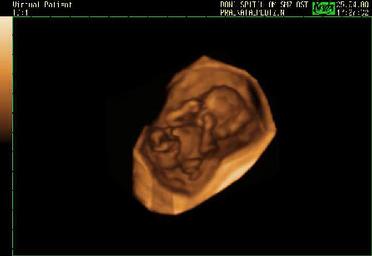

Bryan Howard, president of Planned Parenthood Arizona, on the drop in abortions by 400 after a pro-life law took effect. A law requiring a medical doctor to perform every abortion and meet with the patient 24 hours before the operation to offer her a chance to see the ultrasound.

This quote shows that laws offering women the chance to see an ultrasound of their baby reduce the number of abortions and save children’s lives. This is why Planned Parenthood and other abortion clinics usually turned the ultrasound away from women and discourage them from seeing the images. Here we see that Planned Parenthood is unhappy about the babies who have been born alive because of the laws. Whether this unhappiness springs from loss of revenue or from anti-child sentiment is unclear.